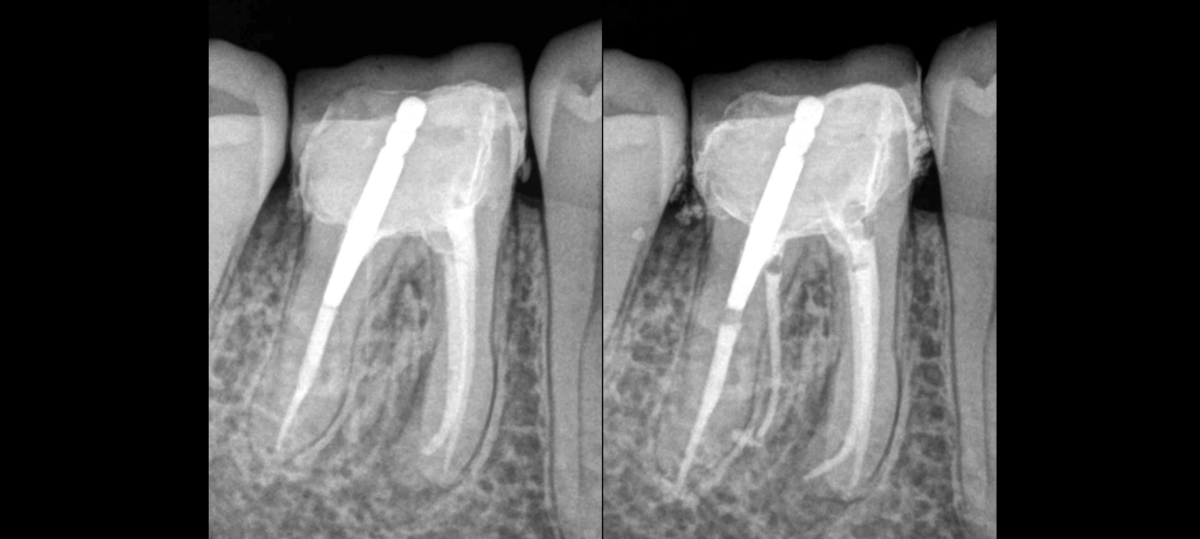

🔍 𝐂𝐞𝐭𝐭𝐞 𝐝𝐞𝐧𝐭 𝐩𝐫𝐞́𝐬𝐞𝐧𝐭𝐞 𝐮𝐧𝐞 𝐩𝐚𝐫𝐭𝐢𝐜𝐮𝐥𝐚𝐫𝐢𝐭𝐞́ 𝐚𝐧𝐚𝐭𝐨𝐦𝐢𝐪𝐮𝐞, 𝐥𝐚𝐪𝐮𝐞𝐥𝐥𝐞 ?

🦷 3 canaux mésiaux ?

🦷 3 canaux distaux ?

🦷 Un isthme reliant les canaux MV – ML tout le long de la racine ?

🦷 Une racine supplémentaire ✅